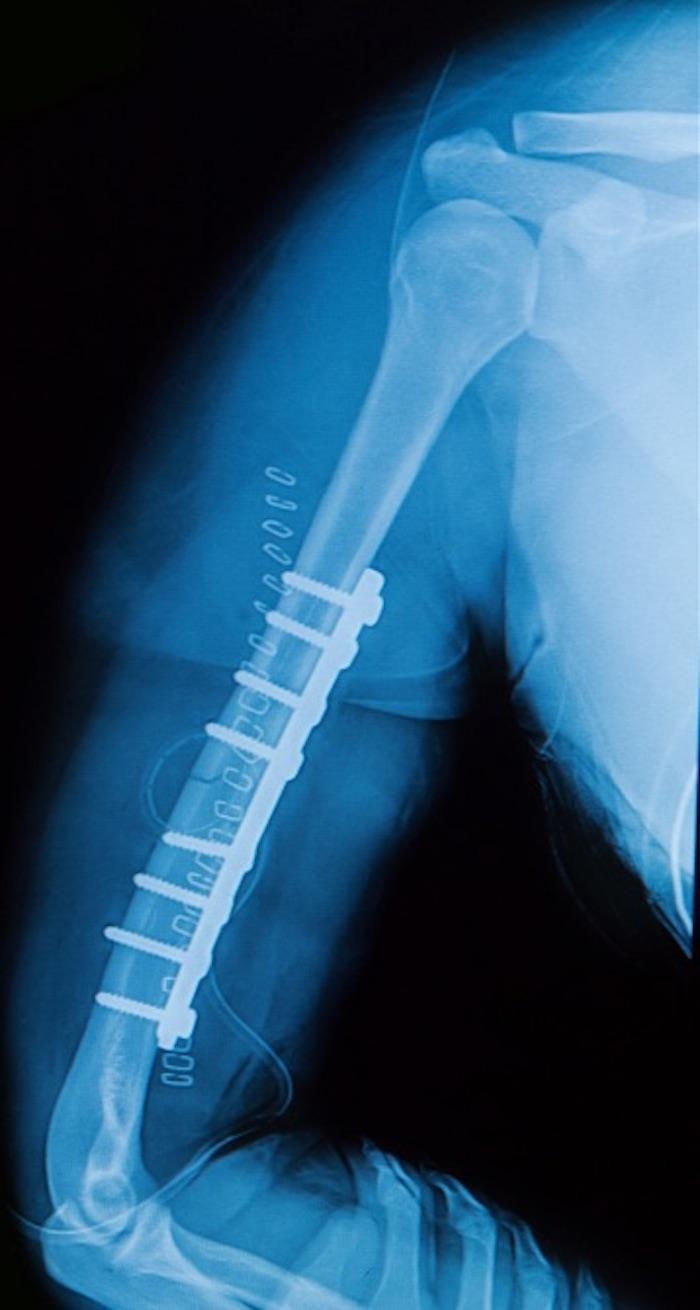

We use plates, screws, or pins to restore alignment by attaching them to the outside of the broken bone. On the other hand, we insert a rod into the center of the bone to hold the break together.

Rods aren’t right for every type of fracture. Instead, they’re most helpful for those involving long bones in your lower body, like the thigh or shin. In these cases, Dr. Tadje inserts a titanium rod into the hollow center of the bone.

Once he inserts an IM rod, Dr. Tadje screws it in place at the top and bottom of the bone to ensure a secure fit. In most cases, rods stay inside your bone permanently, even once you’ve healed.